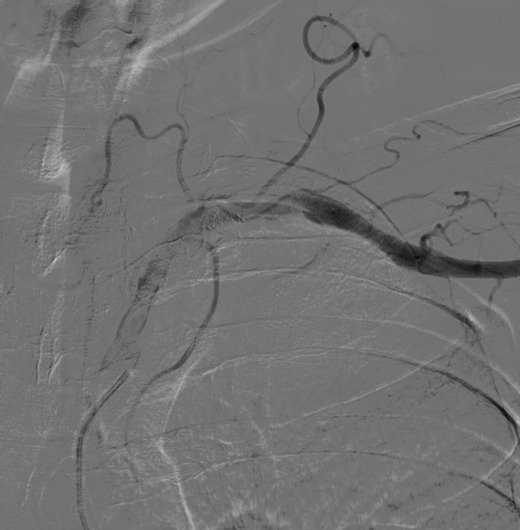

Outcomes observed in patients treated with image-guided, minimally invasive vascular procedures.

Results vary by patient and condition. Images are for educational purposes only.